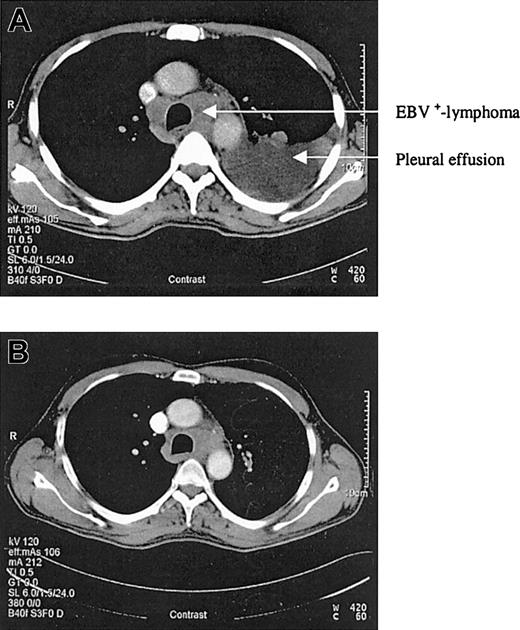

CT scans before and after rituximab application. (A) CT scan of the chest in April 2003. (B) Control CT scan after 4 applications of rituximab showing a good partial response.

We report a case of acute EBV-associated B-cell diffuse large-cell lymphoma developing shortly after successful treatment of relapsed hairy cell leukemia. In 1998, a 46-year-old patient presented with splenomegaly, leukocytopenia, and thrombocytopenia. The peripheral blood smear demonstrated atypically appearing lymphocytes, resembling hairy cells. The bone marrow biopsy confirmed the diagnosis of hairy cell leukemia by May-Grunwald-Giemsa (MGG) staining, alkaline phosphatase antialkaline phosphatase (APAAP), and immunophenotyping with 85% cells positive for CD103. The patient was treated with continuous intravenous infusions of cladribine (3 mg/m2) for 7 days. His blood counts nearly normalized over the next months, and follow-up bone marrow biopsies confirmed a complete remission. However, in December 2002 a progressive leukocytopenia was detected and in January 2003 a relapse of the hairy cell leukemia was diagnosed by bone marrow biopsy with a 39% infiltration of the bone marrow. Cladribine was initiated again as salvage therapy for 7 consecutive days (3 mg/m2). At 3 weeks after completing the chemotherapy cycle, the patient developed fever, dyspnea, and cough. A computed tomography (CT) scan of the chest revealed typical aspergillosis infiltrates and pleural effusions. The aspergillus antigen in the serum, however, was always negative. Surprisingly, in several blood cultures and in the pleural effusion, high amounts of EBV DNA were detectable by polymerase chain reaction (115 000 genome equivalents/mL in the serum and 950 000 genome equivalents/mL in the pleural effusion). Broad spectrum antibiotics, voriconazole, and cidovir were initiated, leading to clinical improvement and regression of lung infiltrates and pleural effusions. To assess the pneumonia, a control CT scan was performed in April, which revealed regress of infection but also a new mediastinal mass and multiple new cervical lymph nodes (Figure 1A). The biopsy of a cervical lymph node revealed a CD20+ B-cell diffuse large-cell lymphoma that was EBV-associated with expression of latent membrane protein 1 (LMP-1) and EBV nuclear antigen 2 (EBNA-2+) (Figure 2). There was no sign of an infiltration by the hairy cell leukemia in the respective lymph node. At this time the hairy cell leukemia was in complete remission, measured by peripheral blood and bone marrow cytomorphology as well as multiparameter immunophenotyping. In this patient there was no previous history of congenital immunodeficiency. In addition, to exclude an HIV infection an HIV test was performed, which was negative. CD4 counts during this period of time, however, were not measured.As the infection was still not under definitive control and the patient's performance status was reduced, we felt that chemotherapy was not feasible. Therefore, a monotherapy with anti-CD20 monoclonal antibody (rituximab) was initiated at a dose of 375 mg/m2. Currently, the patient is in good general condition and follow-up CT scans revealed a good partial response 3 weeks after 4 applications of rituximab (Figure 1B).